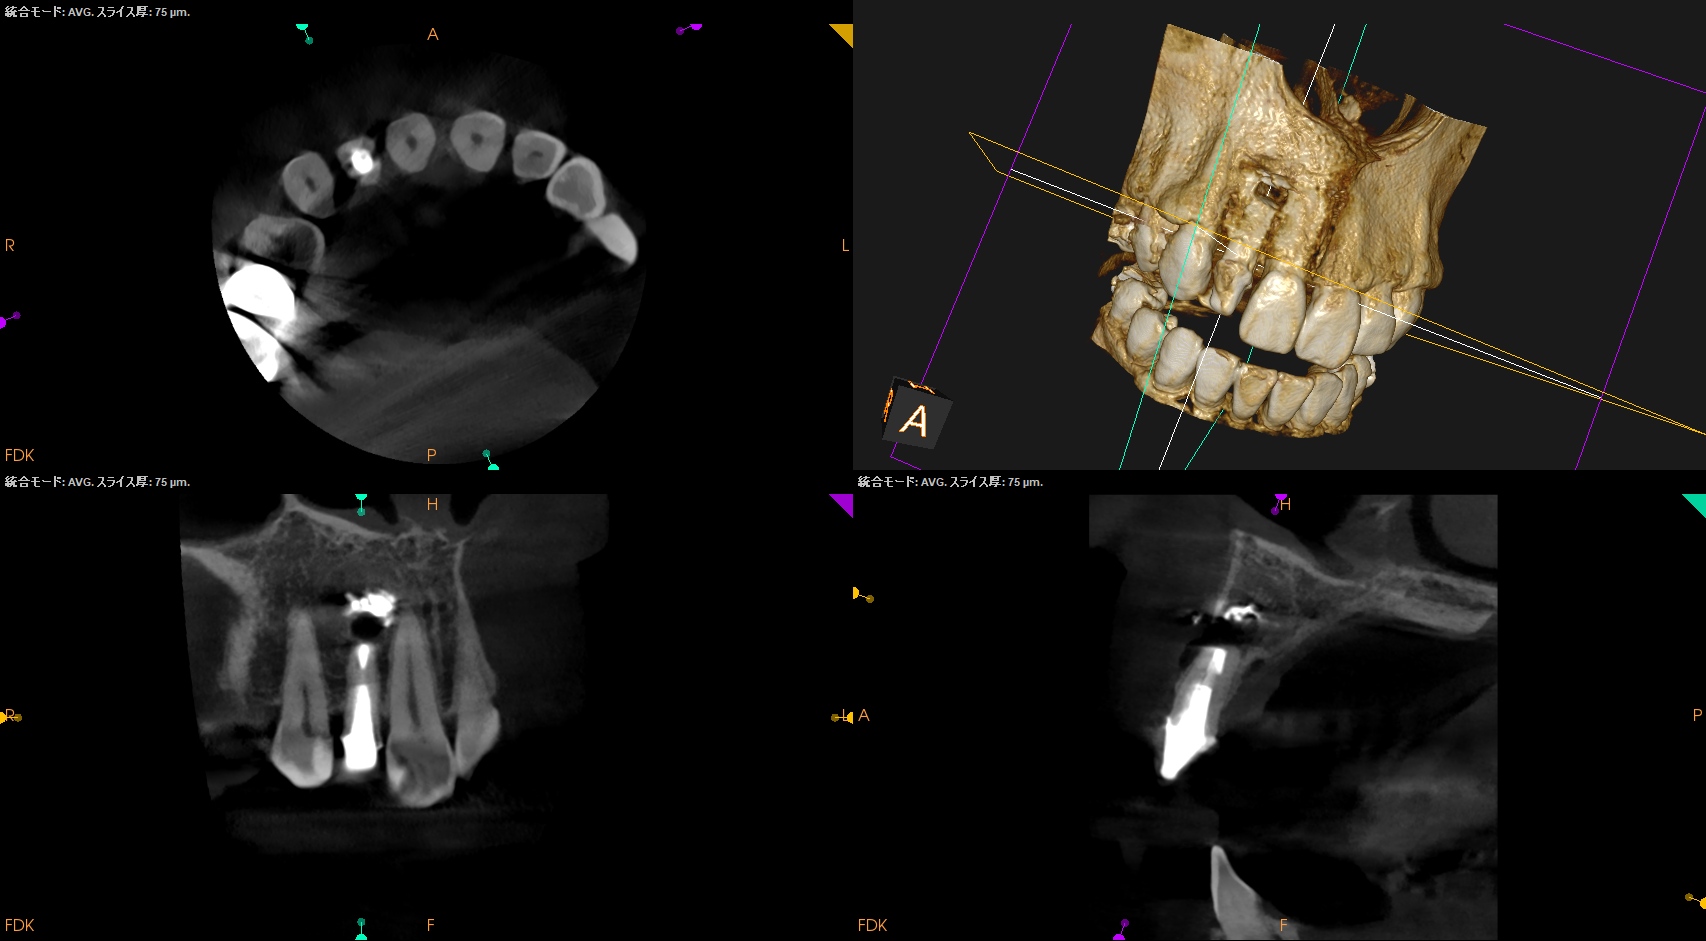

CBCT(2025.10.21)

外科は以下のように行うだろう。

Apexよりも12.5mm下方に#7のApexがあり、そこを3mm切断しようとすれば頬舌的に3.9mの切断が必要だ。

全く難しくはないだろう。